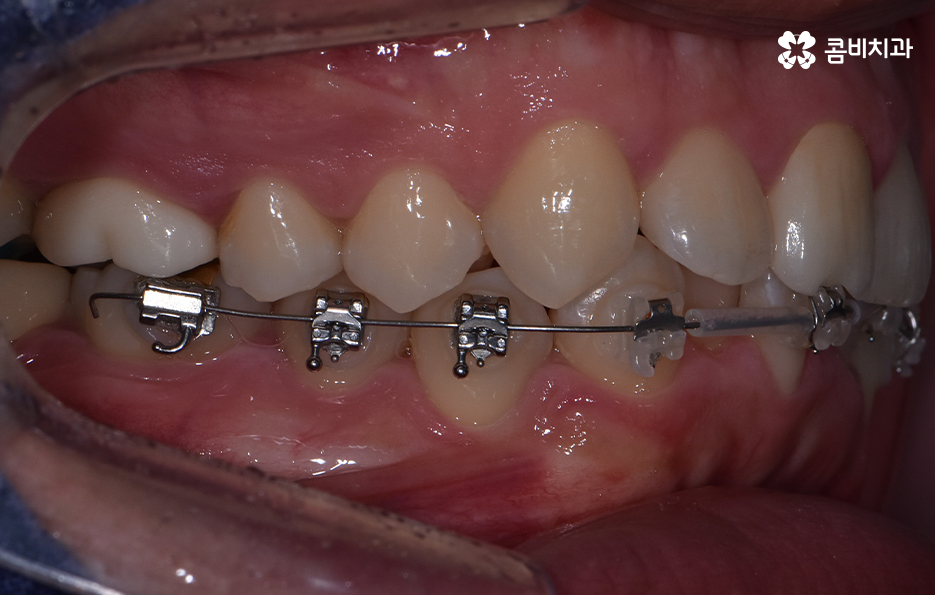

하지만 위에 보시는 환자분의 사례는 윗니와 아랫니의 교합을 고려하고 얼굴형, 골격 등을 고려했을 때도 아랫니만 교정이 가능했던 사례인데 일반적으로 윗니가 아랫니를 살짝 덮고 있어야 하는데 아랫니의 앞니 부분이 유독 안으로 들어와 있었기 때문에 아랫니교정 만으로도 치아교정이 가능했던 사례라고 보시면 좋을 거예요

위 환자분의 사례로 보면 아랫니 중에 하나가 유독 앞으로 튀어나와 있고 나머지 치아는 안으로 들어가 있기 때문에 교합으로 따져볼 때는 아랫니를 전체적으로 앞으로 이동시켜야 했기 때문에 비발치로도 충분히 교정이 가능했고 아랫니교정 만으로도 치료가 가능했어요